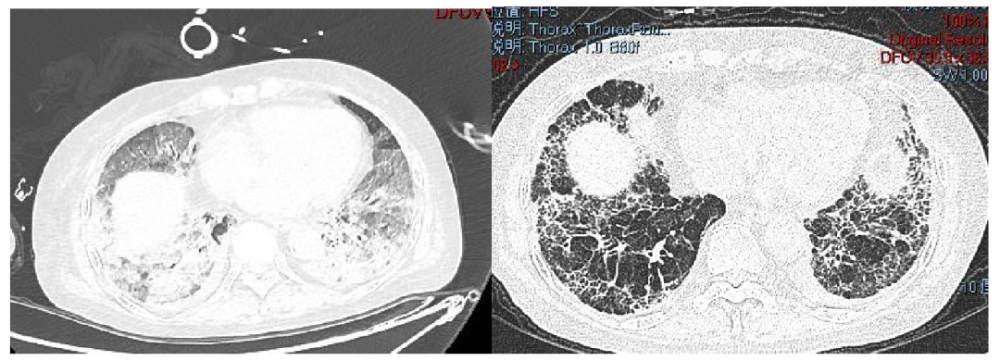

肺纖維化高發

《Nature Medicine》2021年發表了“Post-acute COVID-19 syndrome”,研究指出呼吸困難在60-100天的隨訪期內的發生率為42%-66%,有6.6%的患者因持續低氧血癥需要補充氧氣。患者出院后3個月評估發現約25%的輕度至中度病例存在纖維化,在重癥病例居多的隊列中,約65%的康復者存在肺纖維化。